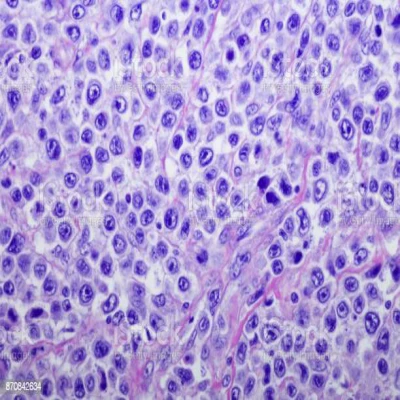

Microscopic picture

In the microscopic section of 's lymphoma, polymorphous cancer cells appear. Cancer cells in the case of lymphoma are called Reed-Sternberg cells, and they are characterized by a large nucleus and they are rich in cytoplasm (fig 2) and surrounded by lymphocytes and macrophages.[5]